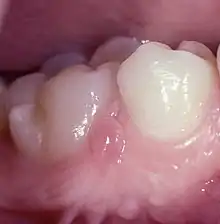

The lesions are bilaterally situated in the attached gingiva or close to the border of the mucosa lingual to the two mandibular canines (Fig.1).[6]

Fig.1.Retrucuspid papillae lingual to both lower canines.

However, they could in a few individuals also be seen simultaneously in the molar region and on the lingual side (Fig.2).[7] They were 2–3 mm wide and high and covered with normal mucosa. Their tips were erected or could be folded down, mimicking the entrance of a periodontal abscess, but no duct was present.

Fig.2. Retrocuspid papilla in molar region labial gingiva mimicking a periodontal abscess

Radiographs showed no bone destruction and the depths of the periodontal pockets could not explain the presence of the lesions. They were nonsymptomatic and were not noticed by the patients.[8]